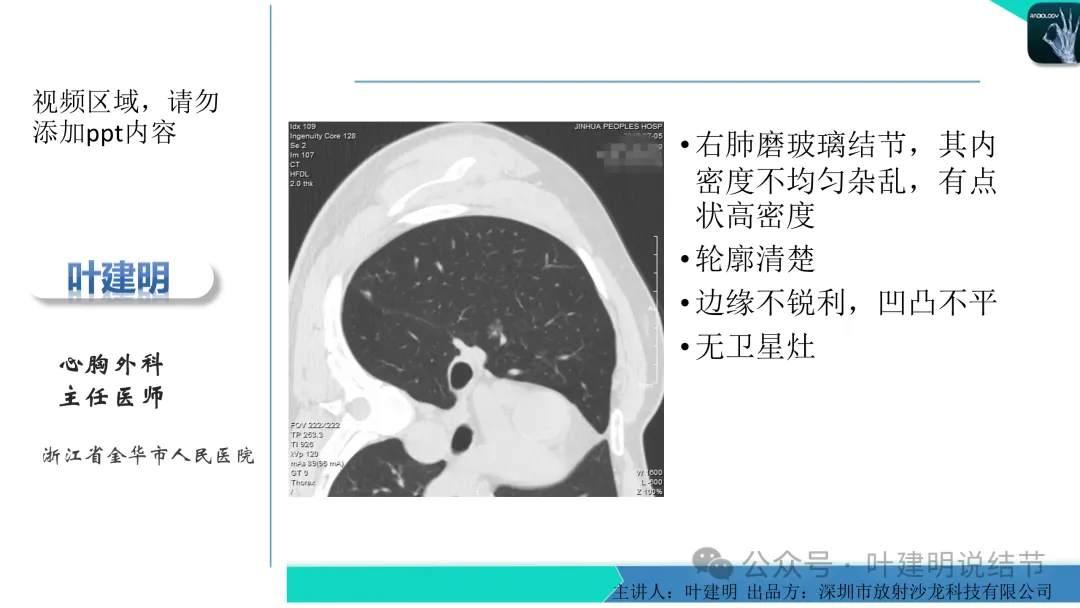

早在2020年时,我受邀在《放射沙龙》做过一个系列的精品课,当时专门总结分析过各类良恶性肺结节与肿块的影像特征,这是当时关于微浸润性腺癌影像特征的分析,今天看来仍基本不太需要改变,大家有兴趣的可以参考: